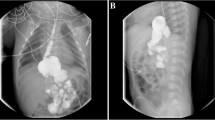

Lymphatic imaging of the lower limbs showed lymphangiectasis and bilateral widening of the venous angle in the mediastinum. Imaging at 1.5 h showed diffuse radioactive uptake in the small intestine, which diminished by 5 hours but at which time showed new areas of radioactive uptake in the ascending colon. Whole body lymphatic imaging indicated widening of the lymphatics in both lower limbs and a flaky radioactive enhancement shadow was seen in the abdominal cavity within 3 h. By 6 h, the hepatic flexure and transverse colon could be visualized.